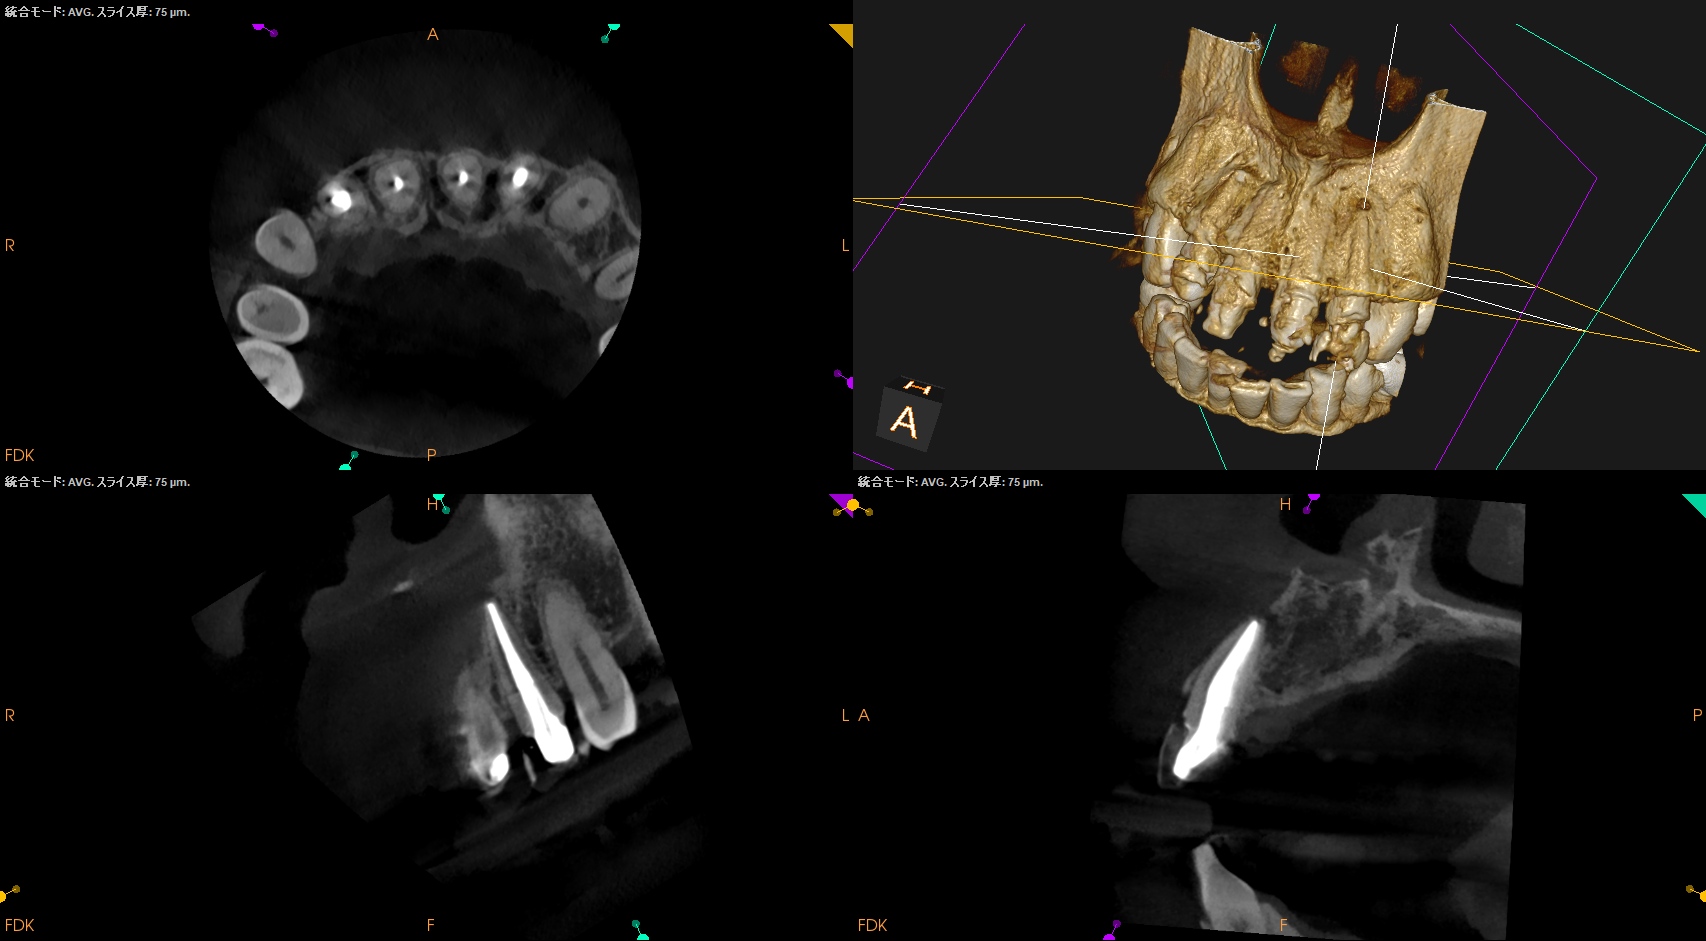

CBCT(2025.1.16)

#7

頬側皮質骨が消失している。

これが圧痛の原因だろう。

#10

#10も#7に同じである。

根管形成・当該部位への根管充填がほぼなされていないように見えることから, 再根管治療へ移行した。